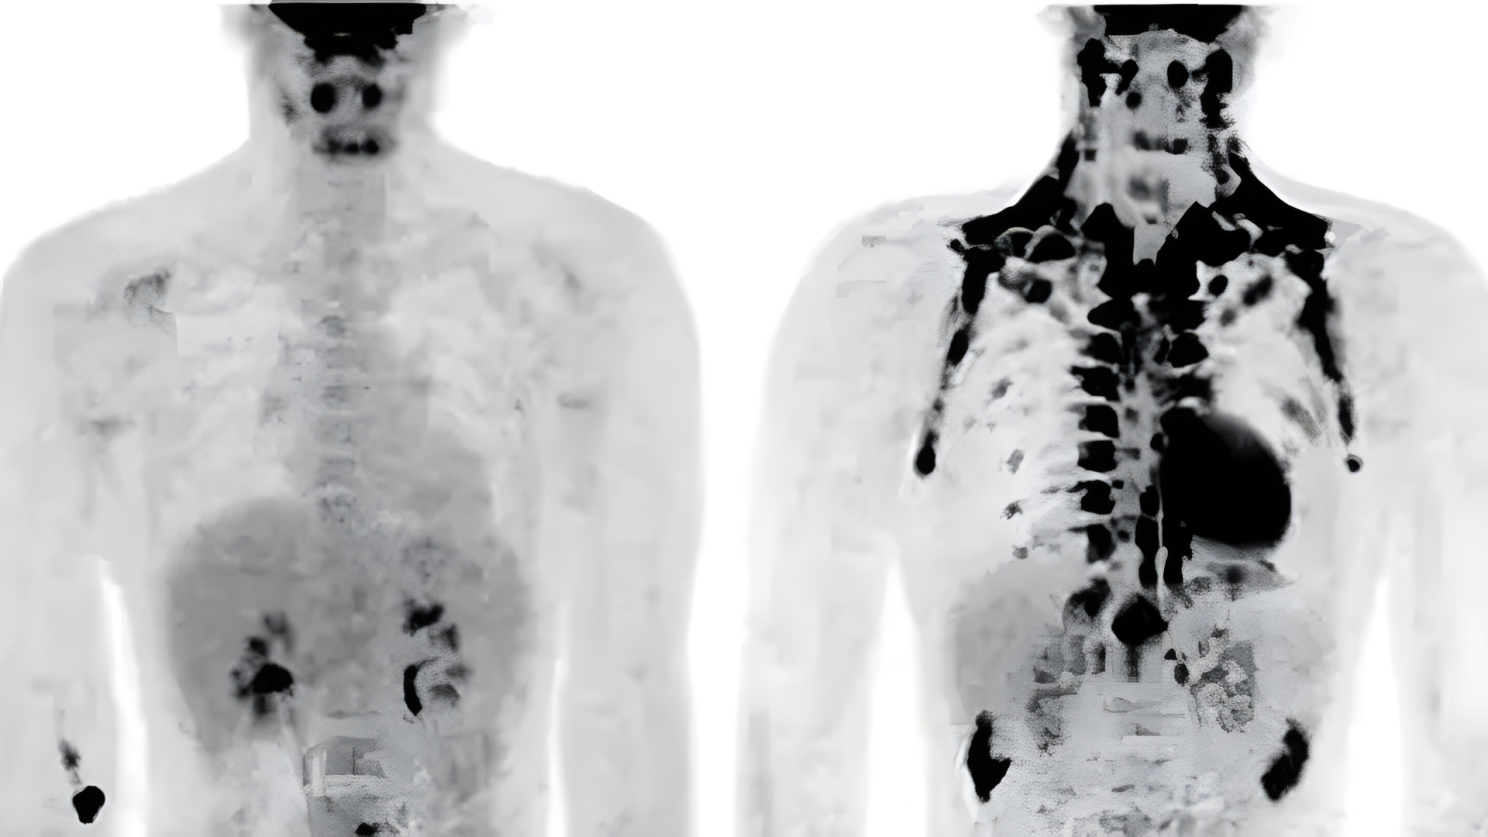

For decades, scientists believed brown fat disappeared after infancy. But in the early 2000s, researchers using PET scans made a surprising discovery: adults have functioning brown fat too. Since then, research has exploded around understanding how to activate and support this remarkable tissue.

In newborns, brown fat makes up about 2% to 5% of total body weight and is concentrated in the back, neck, and shoulders. This helps babies maintain body temperature since they can't shiver effectively. As we age, the amount of brown fat decreases and its distribution changes.

In adults, brown fat is found in smaller deposits around the neck, collarbone area, kidneys, adrenal glands, and along the spine. The amount varies significantly between individuals. Leaner people and those regularly exposed to cold temperatures tend to have more active brown fat than others.